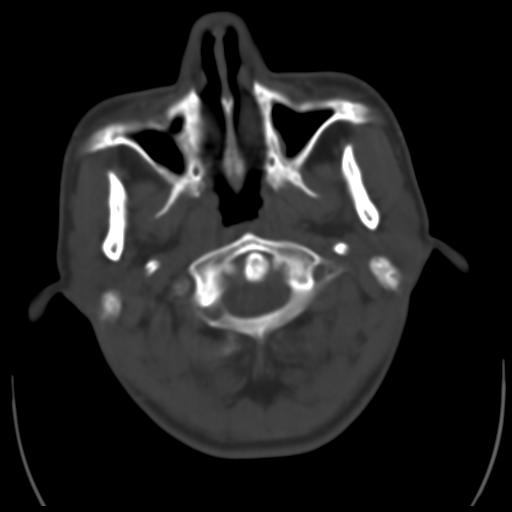

35m 鼻子时不时流血,头及右侧面部痛,颈部淋巴结未见明显大

这个东西大家仔细看看呀

鼻咽血管纤维瘤?

考虑中线肉芽肿(鼻硬结病),次之tb或真菌感染性肉芽肿,病变形态不像肿瘤,建议增强及活检。

acc?淋巴瘤?